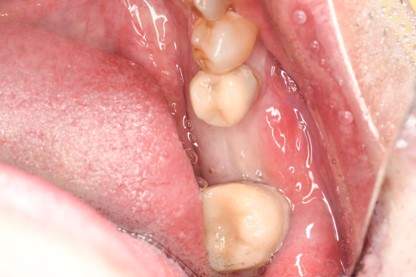

インプラント治療の症例4

口腔内写真

- Befor

- After

| 年齢 | 50代・男性 |

|---|---|

| 主訴 | 部位:左下6番7番 主訴:左下奥歯腫れて痛い。 |

| 治療内容 | 左下6番抜歯、左下6番7番骨造成、インプラント埋入 |

| 治療費 | 合計:1,232,000円 ・内訳 診断料:55,000円 サージカルガイド2本:66,000円 GBR:110,000円×2本 埋入料:165,000円×2本 静脈内鎮静麻酔:77,000円 2次OPE:22,000円×2本 仮歯:55,000円×2本 上部構造(フルジルコニア):165,000円×2本 (2023年1月現在) |

| 治療期間 | 約8ヶ月 |

| リスク・副作用 | リスク・副作用 |

| 治療方針 | 元々支台歯に負荷がかかりやすいとされている延長ブリッジを抜歯し、1本単体でしっかりかめるようにインプラントを2本埋入した。骨吸収も進んでいたため、※GBR法で骨造成を同時に行った。 治療と並行して、全顎的な歯周病治療も行い、今後は歯周病が進行しないよう、こまめにメンテナンスに通っていただく。 |

| 特記事項 | ※1 GBR・・・骨再生誘導法。骨の高さや厚みを人工骨や人工膜などを使用し再生する方法 |

| 担当者所見 | 6番は歯根分割された被せ物が7番の欠損部との延長ブリッジとされており、強い咬合と歯周病も相まって負荷がかかり動揺し、歯として機能しなくなったため、抜歯となった。 |